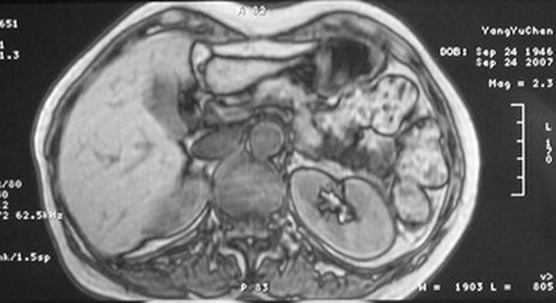

标题: MRI2066:腹膜后占位,请会诊,CT18531近期扫描图像

无明显不适,体检发现,

mri基本排除血管类肿瘤,明显强化说明极富血供,临床无症状,考虑胰岛细胞瘤可能大。

强化明显,并见有血管与之相连;考虑巨淋巴增生症.

极富血供的占位性病变,首先考虑良性,期待结果。